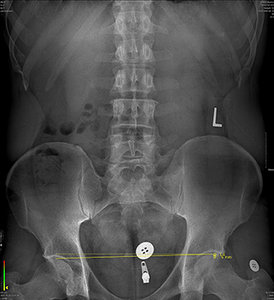

FIG 1 Barefoot standing X-ray.

All that being said, the human body has an amazing ability to adapt. These underlying conditions can be present for years without sign or symptom. However, each body reaches its limit at some point. This sudden failure to adapt can occur due to trauma, a sudden increase in mechanical stress or mechanical stress being applied consistently over time. Whatever the case may be, the result is a symptom.

On the other hand, the symptoms may have been present for years and years in the form of low back pain, but no one made the connection between lower extremity mechanics and the low back. How many chiropractic patients are treated for weeks, months and years for LBP without ever being evaluated for a clinically significant structural imbalance?